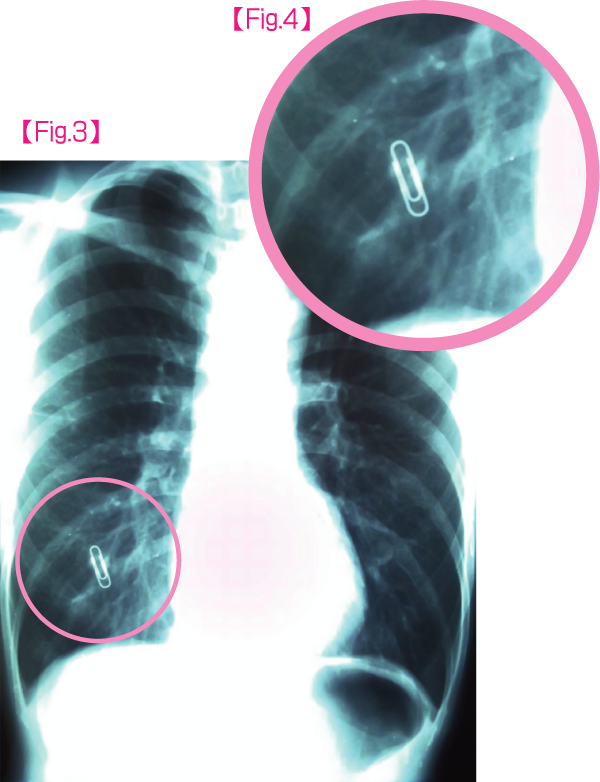

女性の場合は乳頭の影が肺に重なって写ってしまうことは珍しくなく、肺がんなどの病変と見分けがつかない場合もしばしばです。

当院では、乳頭の可能性が高い影があった場合【Fig.1(病変拡大Fig.2)】には、乳頭部にご自身で金属クリップを張り付けていただいて再撮影【Fig.3(病変拡大Fig.4)】して、2枚のフィルムを比較して、影が乳頭に一致することを確認しています。